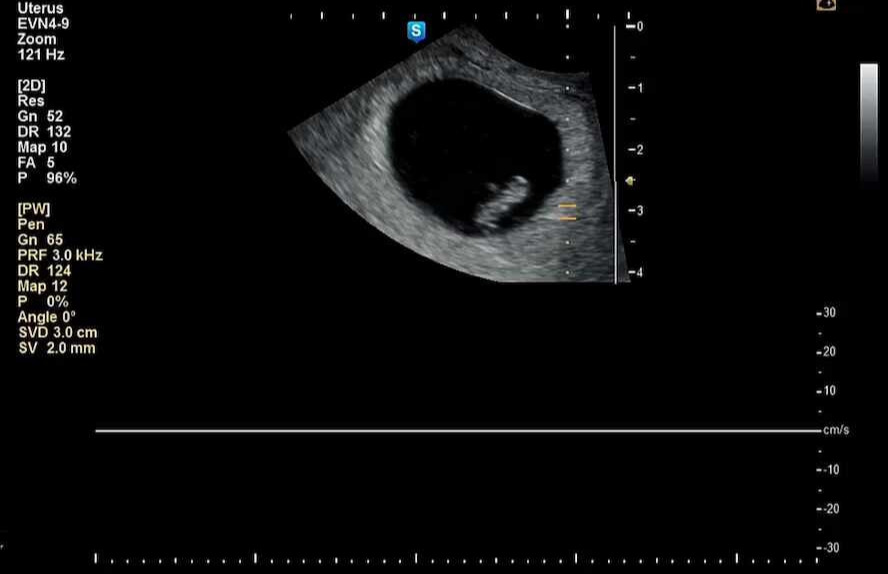

외관상의 변화는 거의 없기 때문에 내 안에 뭐가 있나? 싶던 7주 차에 병원에서 튼튼이의 심장소리를 처음으로 듣게 되었다!

8bdc1e01-c918-11ed-b2fb-a0369ffabd48_01.jpg 1cm 남짓한 아이의 몸에서 우렁차게 심장이 뛰고 있었다.

아니 고작 1cm를 는 아이의 심장소리가 이렇게 우렁차다니!

남편과 나 모두 산부인과에서 진한 감동을 받게 되었다.